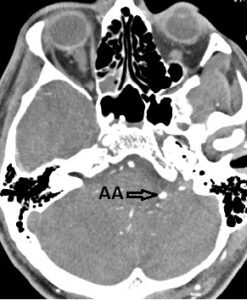

КТ-ангиография. Аксиальная проекция. АА – артериальная аневризма.

Краткая информация о пациенте: Л.С.В, мужчине 1992 г.р. установлен диагноз: «Массивное базальное субарахноидальное кровоизлияние. H-H III, Fisher III». 12.11.2022 г. эвакуирован и доставлен в клинику нейрохирургии ВМедА. При обследовании (МСКТ-ангиография) выявлена диссекционная аневризма левой задней нижней мозжечковой артерии. Для уточнения формы, размеров, локализации аневризмы, определения тактики лечения в неотложном порядке в условиях рентген-операционной под общей анестезией выполнена селективная церебральная ангиография, переведенная в оперативное вмешательство для профилактики повторного кровоизлияния и создания благоприятных условий для скорейшего выздоровления.

Доступ к внутрисосудистому церебральному руслу правосторонний феморальный. При ангиографии из левой ПА визуализируется диссекционная аневризма, размером 3*3 мм, располагающаяся в латеральном медуллярном сегменте левой задней нижней мозжечковой артерии (ЗНМА).